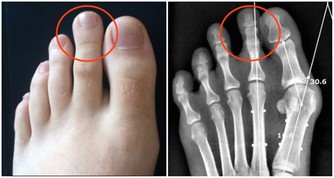

5. 健康問題

如果你睡眠很好、堅持鍛煉、吃得健康,並且壓力有限,但仍然總是很累,那麼最好去看看醫生。

因為下列疾病可以導致過度疲勞:貧血、焦慮症、慢性疲勞綜合症、抑鬱、糖尿病、食物不耐受、心髒病、營養素缺乏症、甲狀腺功能減退症、懷孕、尿路感染等。